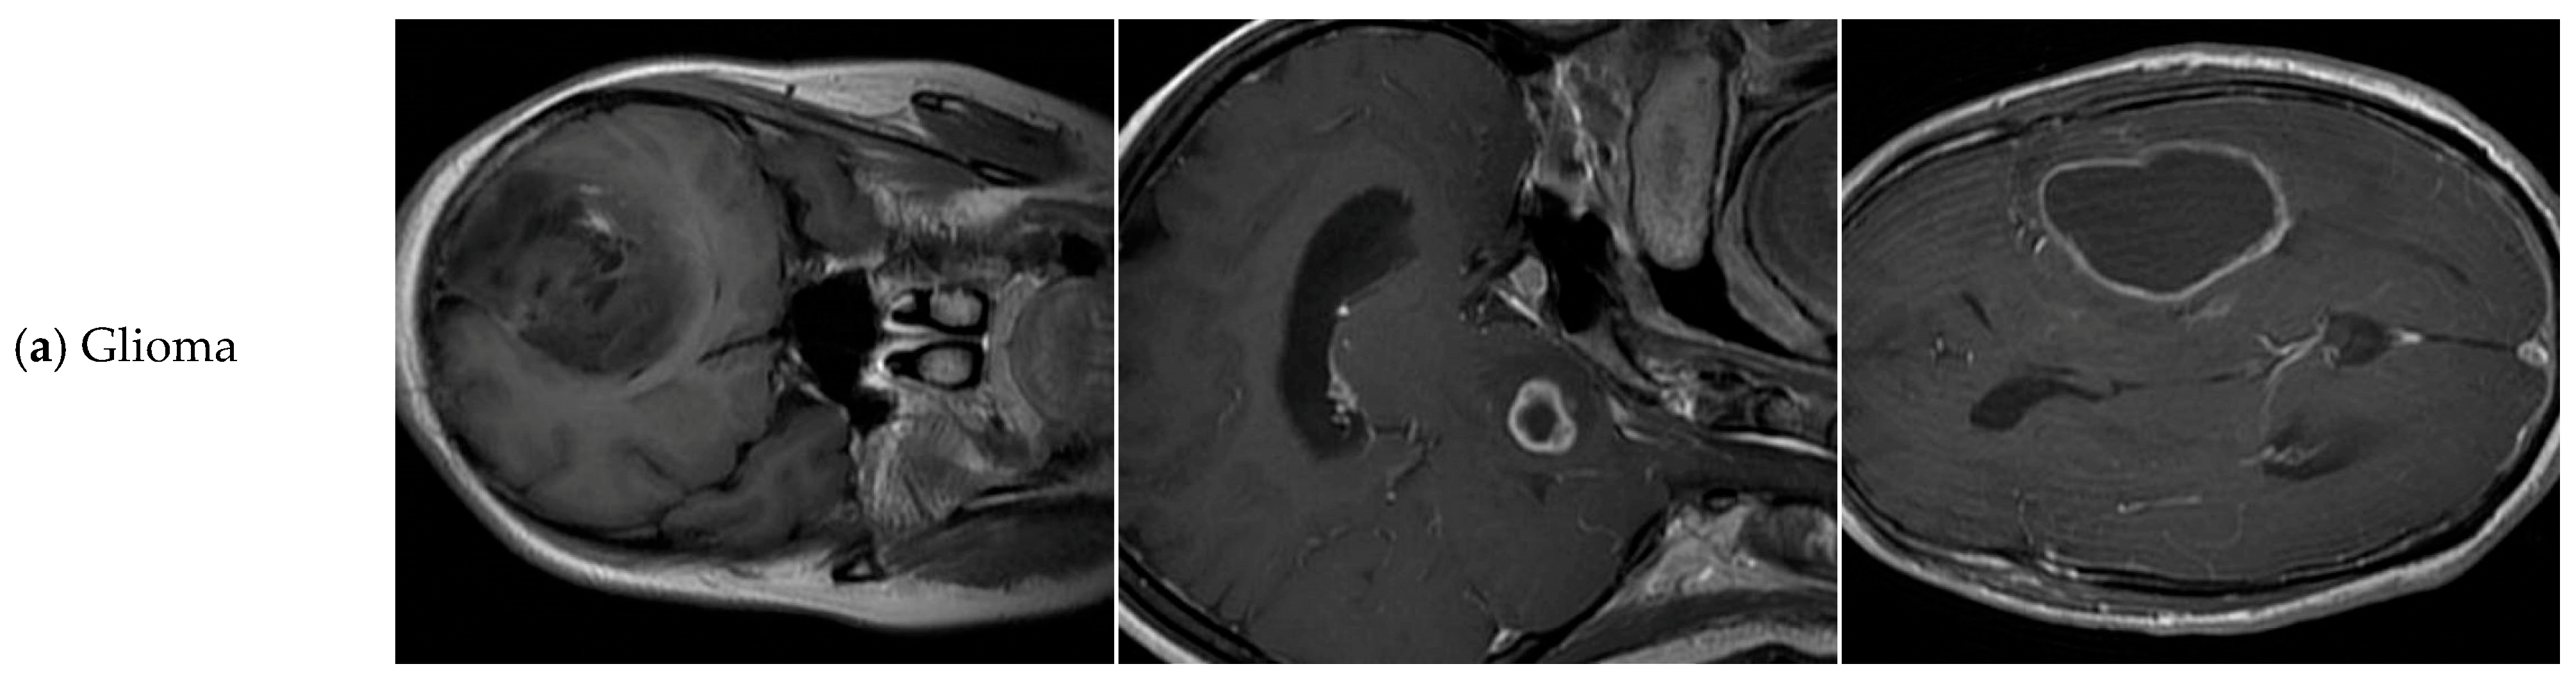

4.1. Dataset

| Tumor-Otak | Total | Glioma | Meningioma | Pituitary Tumor |

|---|---|---|---|---|

| train | 2144 | 984 | 502 | 658 |

| val | 612 | 285 | 142 | 185 |

| test | 308 | 159 | 62 | 87 |